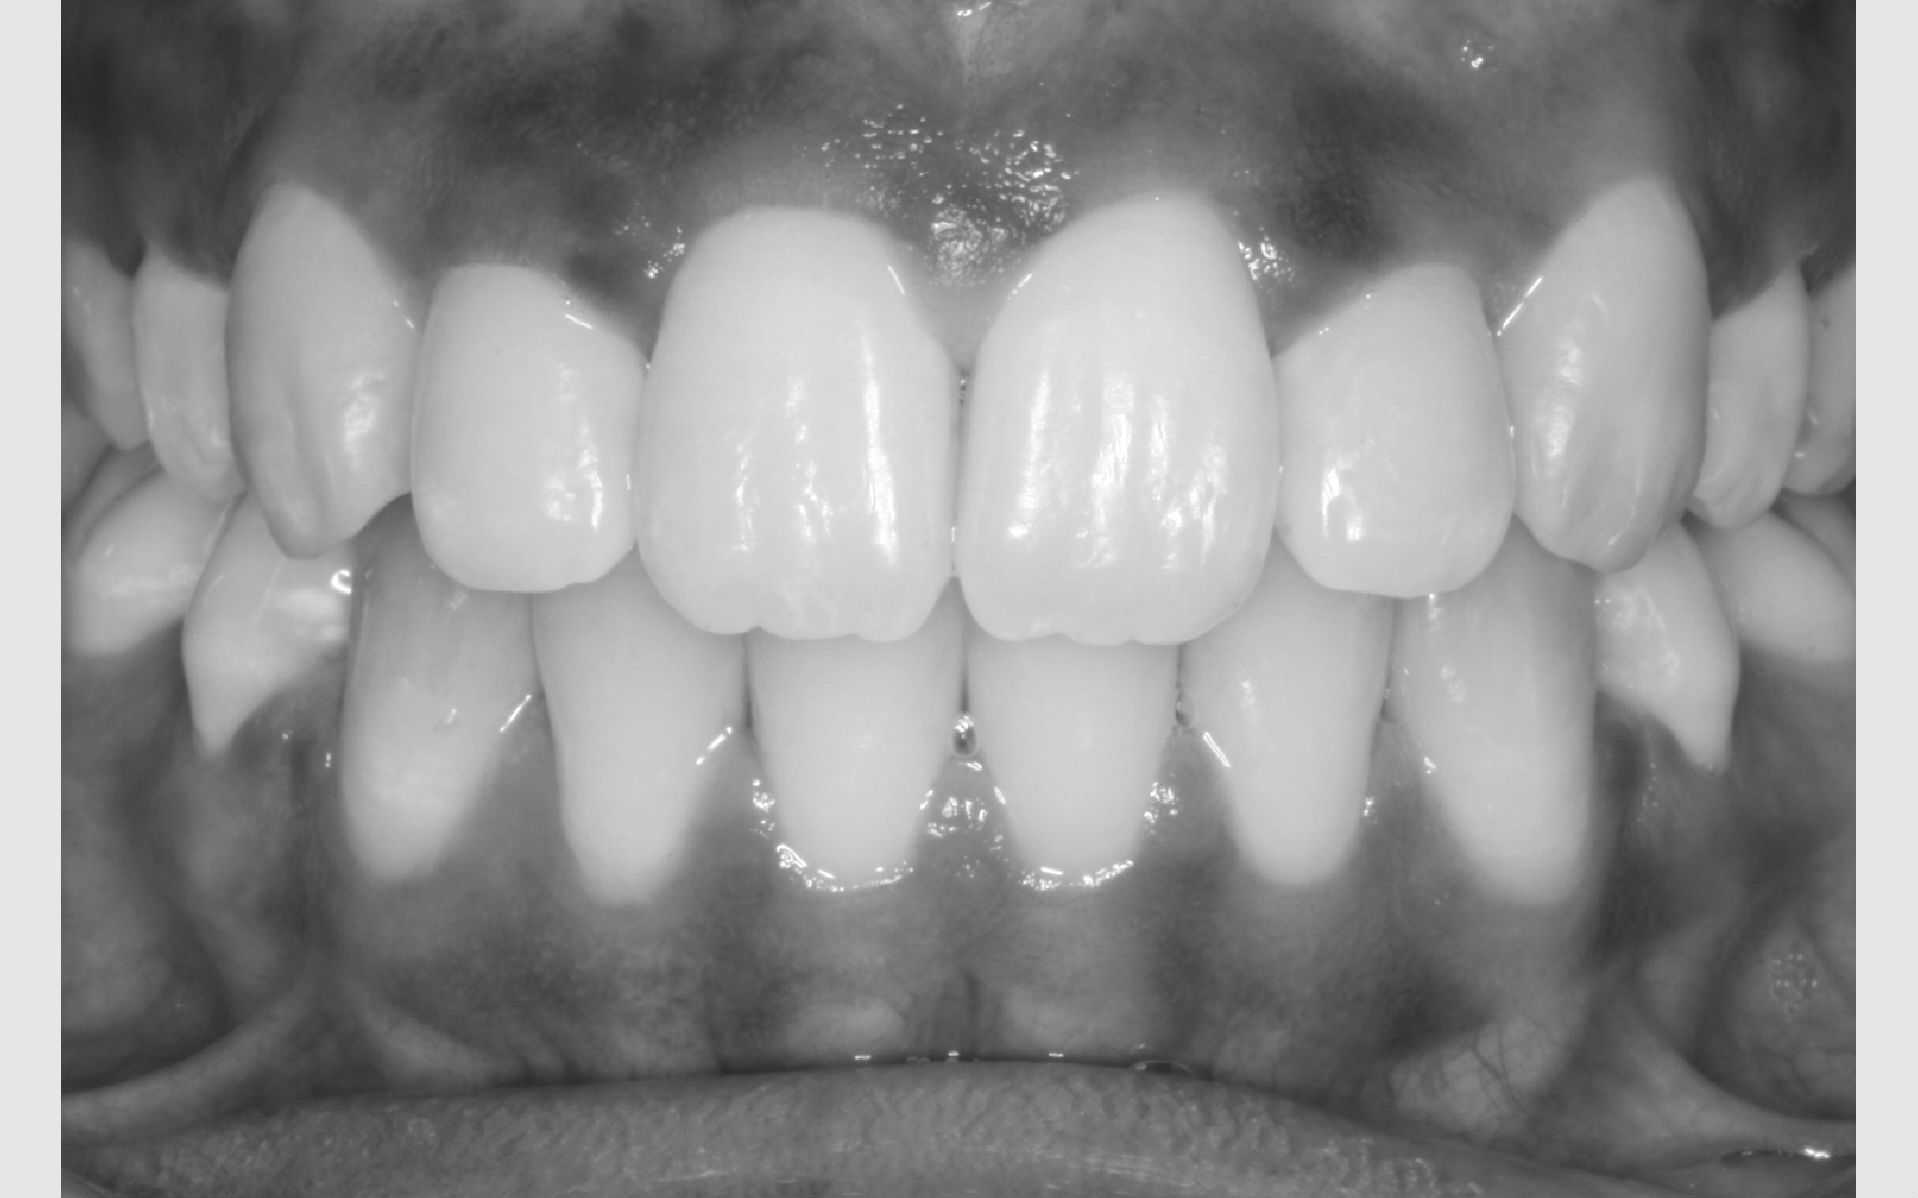

Der bliver taget billeder "udenpå og indeni" samt røntgenbilleder.

Dit barn skal selv holde sine læber til side med en læbeholder, mens tænderne bliver fotograferet. Billederne har følgende formål: